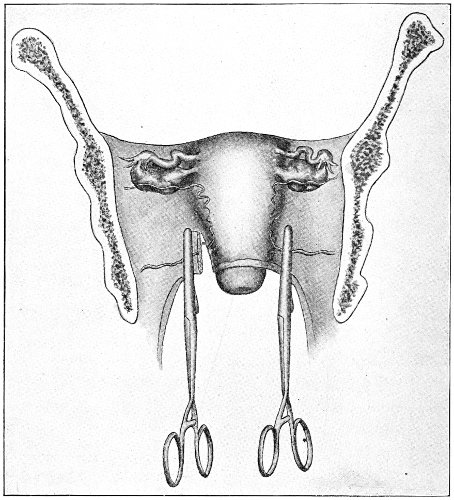

Vaginal and Bimanual Examination.—Having examined and noted the condition of the external genitals, the physician should next proceed to examine the vagina. The index finger of the right or the left hand should be gently introduced into the vagina. The condition of the vaginal walls, and the direction, consistency, form, etc. of the vaginal cervix, may be determined. The shape and size of the os uteri should be noted. The ulnar edge and the tips of the fingers of the other hand should then be placed upon the abdomen, immediately above the symphysis pubis, and gently pressed backward and downward toward the vaginal finger 24 (Fig. 2). In this way the various pelvic organs, the uterus, Fallopian tubes, ovaries, and ureters, may be palpated between the two hands, and their position, size, shape, and consistency may be determined. Such an examination is, of course, made much more easily in a thin woman than in a fat one. A thin woman a few weeks after labor may be examined most easily, on account of the relaxation of the abdominal and vaginal walls.

Fig. 2.—Bimanual examination.

This is called the bimanual method of examination, and the student will find that as he acquires practice in this method he will gradually depend less upon examination by the uterine sound and the speculum, and will rely altogether upon his sense of touch, his ability to palpate.

It matters not which hand be used in making the vaginal examination. It will, however, be found that the hand that is used the more frequently will become the more proficient.

In making the bimanual examination the structures 25 should be palpated methodically in order. The vaginal finger notes the condition of the cervix uteri. If the fundus be in the normal position, the uterus can then be taken between the abdominal hand (upon the fundus) and the vaginal finger (upon the cervix) (Fig. 3). The shape, size, mobility, and consistency are noted. The vaginal finger is then passed anteriorly and laterally toward either uterine cornu, while the abdominal fingers pass over to the posterior aspect of the same cornu. The ovarian ligament and the proximal end of the Fallopian tube may thus be felt. Passing farther outward, the whole of the tube and the ovary may be examined. The same procedure is then applied to the opposite side.

Fig. 3.—Bimanual examination; median sagittal section of the pelvis.

The condition of the ureters may be determined by placing the vaginal finger in either lateral vaginal fornix and drawing it outward and forward, when these structures will pass over the end of the finger. When the 26 ureters are indurated by inflammation they can be plainly felt.

By the method of examination here advised the physician will always make a visual examination before making a digital one. There are several advantages derived from this procedure. In the first place, no examination of a woman is thorough unless a careful visual examination of the external genitals has been made. The discovery of discharges and of lesions of the external genitals may throw much light upon the condition found higher up in the pelvis. Again, the examiner protects himself. A great many unfortunate cases of syphilis have been acquired by physicians from a primary sore upon the examining finger. A preliminary visual examination enables one to guard against this danger. The primary sore occurs upon the end of the examining finger or upon the web between the index and middle fingers—the part of the hand that is pressed against the fourchette.

The hands of the physician should, of course, be surgically clean before making an examination, and the grease or oil which is used as a lubricant should be clean. The hands should always be washed, after separating the parts to make the visual examination, before the finger is thrust into the vessel containing the lubricant. It is best to place a small portion of the lubricant on a plate or a saucer for each individual patient, and thus avoid the danger of contaminating the rest. Carbolized oil, borated vaseline or cosmoline, and a thick sterile solution of soap are good lubricants. Neutral green soap diluted with boiled water to the consistency of thin jelly is a very agreeable lubricant which may easily be washed from the hands and the vagina.

If practicable, the woman should receive a vaginal douche of bichloride-of-mercury solution, 1:4000, and the vulva should be washed, before making a bimanual examination. The examiner should always clean the external genitals of all discharges before introducing the vaginal finger. In this way we avoid the danger of 27 carrying septic material from the external genitals to the upper portion of the genital tract. This preliminary cleansing is not desirable before the external genitals have been examined; for much may be learned from observation of the discharges which bathe or escape from the various structures. If practicable, a cleansing vaginal douche of bichloride-of-mercury solution should be administered after the bimanual examination.

The examination of the uterus and other pelvic structures is often facilitated by dragging the uterus downward with a tenaculum while the vaginal or the bimanual examination is being made. Sensation in the cervix is so slight that little or no pain is experienced in this procedure. The anterior or posterior lip of the cervix is caught with the single or the double tenaculum (Fig. 4), guided along the vaginal finger or introduced through the speculum, and the uterus is drawn down by an assistant in case the bimanual examination is being made, or by the external hand of the examiner in case a simple vaginal examination is made. When this is done the utero-sacral ligaments are made tense, and can be felt like two cords extending from the sides of the cervix outward and backward to the pelvic wall. The posterior surface of the uterus can be palpated often as high up as the fundus. The method is especially useful when the examination is made by the rectum, and in this way the whole posterior surface and the fundus of the uterus may be palpated (Fig. 5).

The contraindications to a vaginal examination are 28 virginity, the presence of a hymen, and any acute inflammatory or painful condition of the vulva or vagina. None of these conditions, however, forbid an examination if an exact diagnosis is essential to the proper treatment of the case, and can be made only in this way. It may be that in these cases a rectal examination will be sufficient for diagnosis.

Fig. 5.—Bimanual examination with one finger in the rectum. The uterus is drawn down with the double tenaculum.

Rectal examination of the pelvic structures is made in a way similar to that already described for the vaginal examination. Bimanual examination may be made by palpating the various organs between the rectal finger and the abdominal hand.